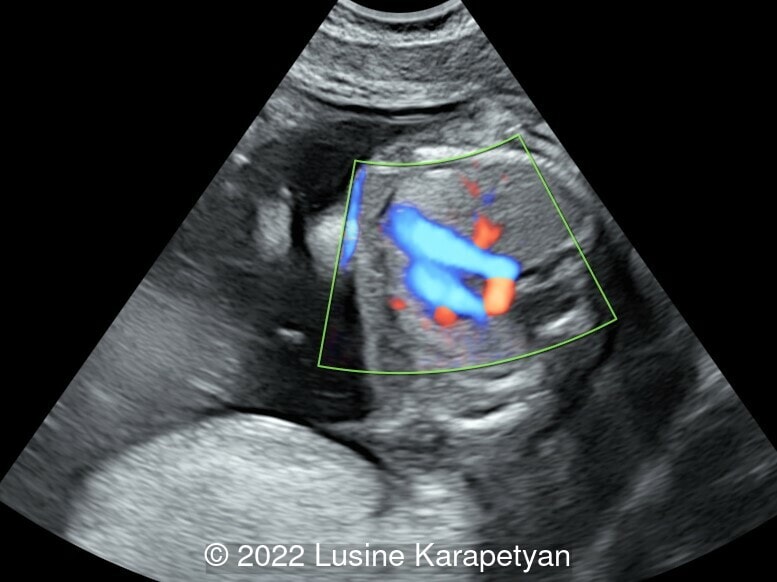

We present a case of double aortic arch. The initial fetal echocardiogram revealed normal intracardiac anatomy, and a double aortic arch with antegrade flow in both arches.

The diagnosis of double aortic arch on prenatal ultrasound is made when the ascending aorta appears to divide into two branches coursing on either side of the trachea. In 70% of double aortic arch cases, the right arch is dominant, but antegrade flow is commonly demonstrated in both aortic arches. The presence of a right aortic arch should prompt more careful evaluation to exclude a double aortic arch. The left aortic arch is often smaller than the right aortic arch, such that visualization of the diminutive left aortic arch is poor and can be overlooked on prenatal imaging [1].

The three-vessel tracheal view is the most characteristic view for double aortic arch diagnosis, but it alone is not enough. When an arch shows atresia, a vascular ring is not always typical due to an interruption in the blood flow of the atretic segment. The differential diagnosis with a right aortic arch then becomes challenging. Therefore, multiple views should be performed to better observe the origin, course, and branches of the two arches. The following steps and key points for systematic examination are recommended:

- The three vessel trachea view is used to identify a complete O-shaped vascular ring formed by the left and right arches surrounding the trachea and esophagus. Because these two arches may not be at the same level, the probe may need to be slightly tilted.

- In order to better display a small non dominant arch, reduce the scale of blood flow velocity in the color Doppler mode. It can be difficult to identify the fibrous cord formed by a partial atresia of the nondominant arch, therefore the vascular ring can be diagnosed indirectly by identifying the blind end or diverticulum of the arch. When the left arch is small and difficult to visualize, the right arch should not be mistaken for the right pulmonary artery, which would be travelling in the same direction [2].